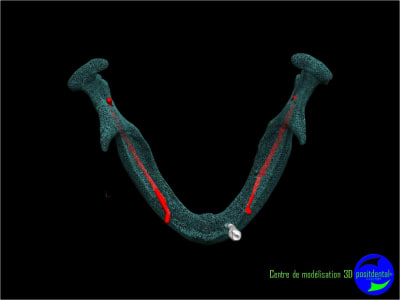

Il faut faire une ostéotomie en forme de tube au niveau de 33 et 43 et y placer deux tiges cylindro-coniques en titane. Quelques mois après tu pourras t'en servir pour fixer la prothèse.

Résorbée genre comme ça?